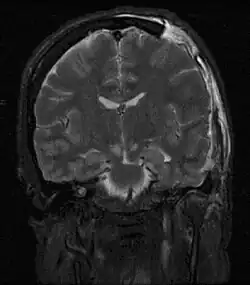

![]() | |

| MRI showing injury due to brain herniation | |